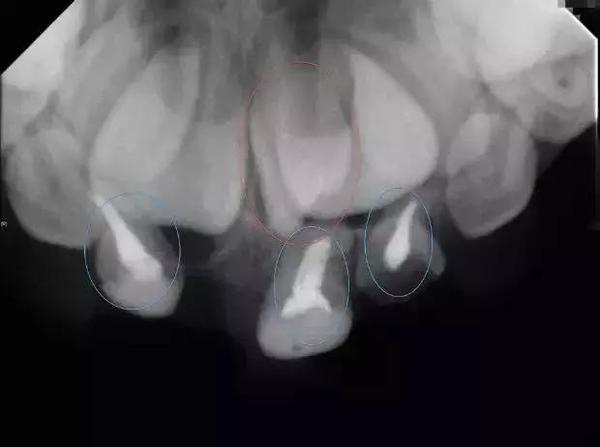

▲咬合片:藍圈處,是作過根管治療的三顆乳牙。這三顆乳牙上方有二顆門牙的恒牙,紅圈處是卡在門牙間的多生牙,會(hui) 影響門牙的萌發。